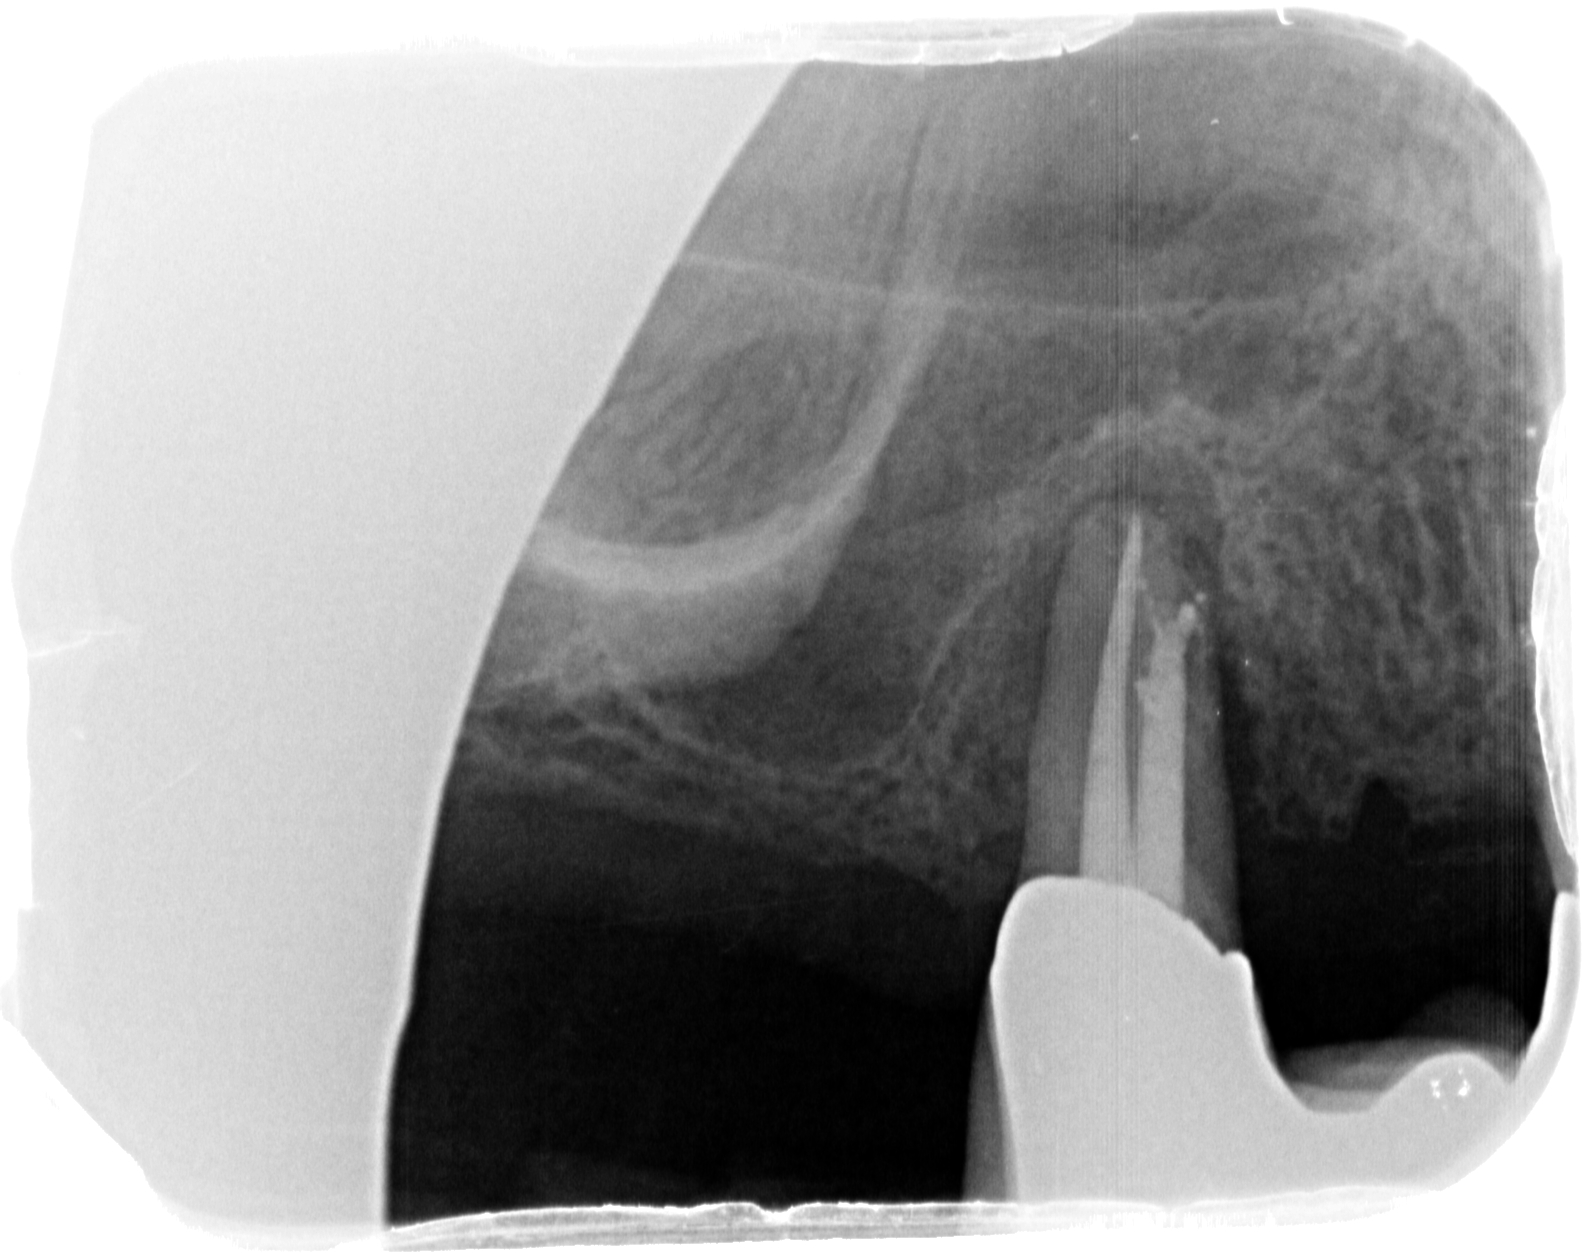

WF mit Stufe bukkal und Seitenkanal – Rö exzentrisch Veröffentlicht 24. Juni 2013 am 1582 × 1253 in Endo- Paro – Läsion